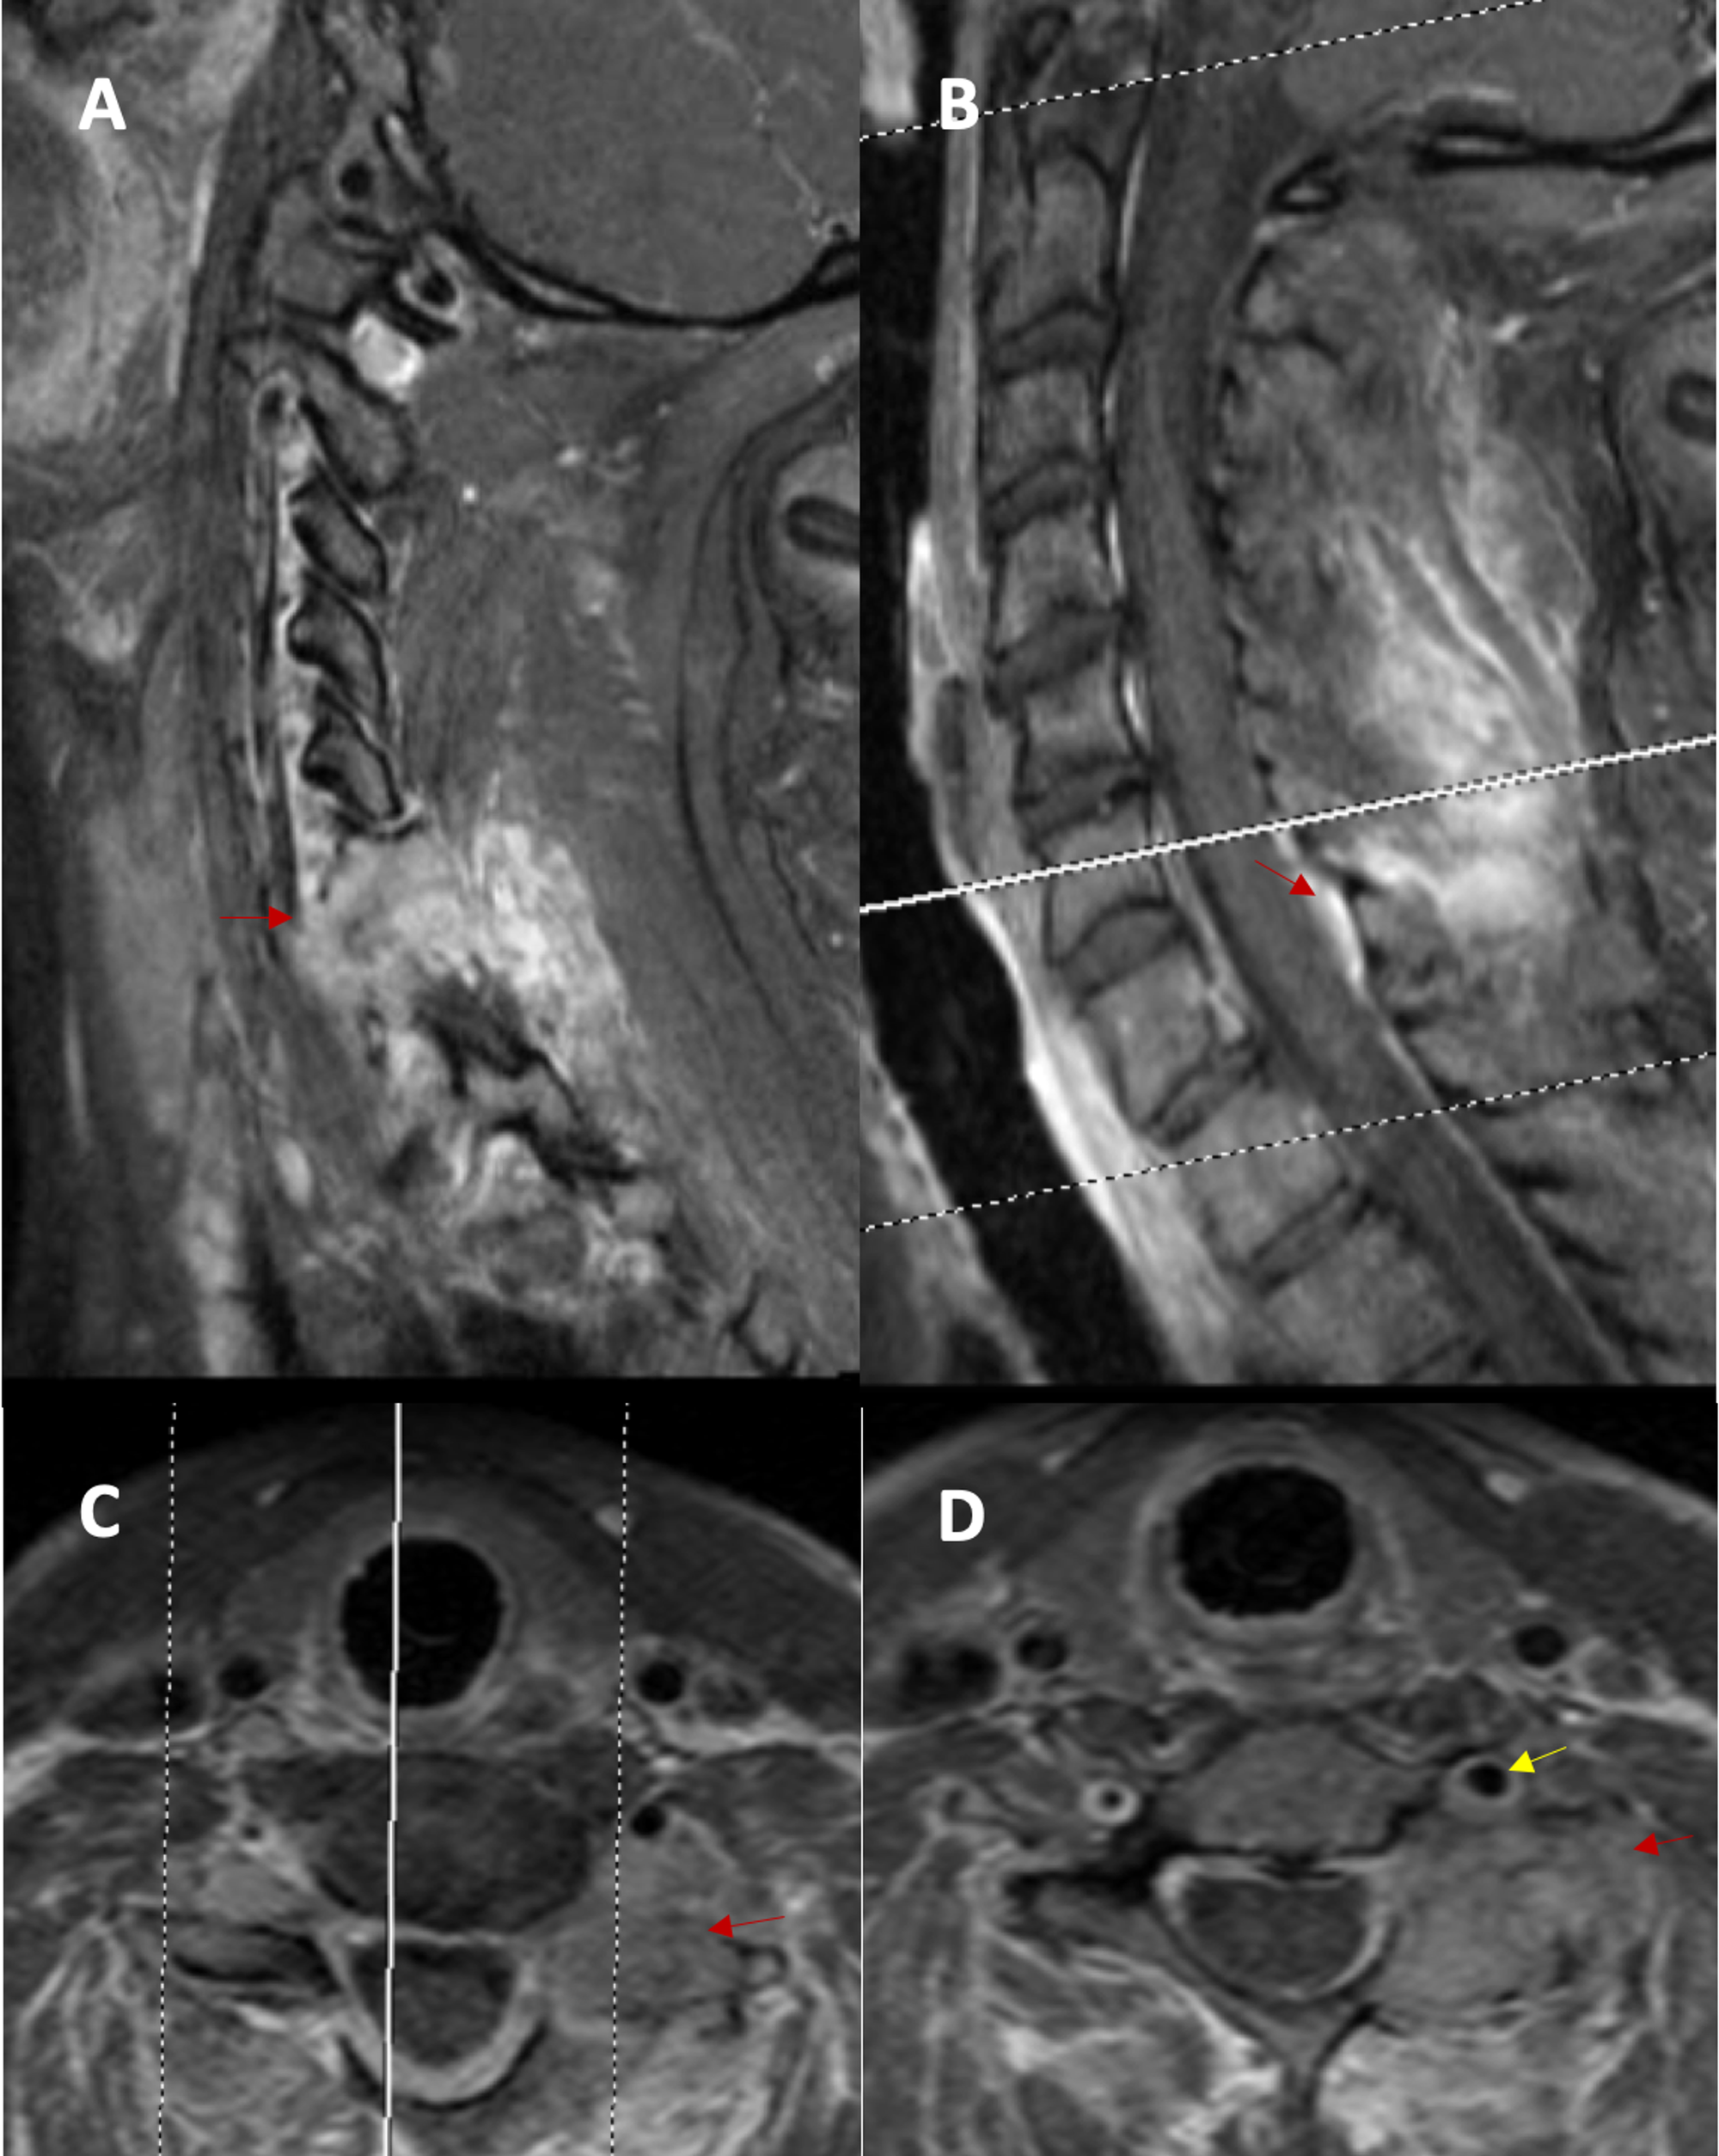

From www.cureus.com

Cureus Tenosynovial Giant Cell Tumor of the Cervical Spine Case What Is A Cervical Mri Without Contrast Mri with and without contrast is done because it allows better detection and diagnosis of abnormalities. What is a cervical spine mri? A normal cervical spine mri typically reveals a symmetrical alignment of vertebrae, with clear spacing between the. A cervical mri (magnetic resonance imaging) scan uses energy from strong magnets to create pictures of the part of the spine. What Is A Cervical Mri Without Contrast.